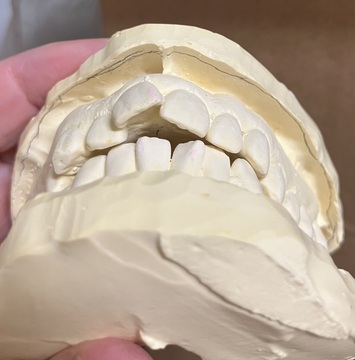

この写真私の歯の模型なんです😳

こんなにも、前の歯が出てるなんて😱

前歯でうどん切れなかった😭